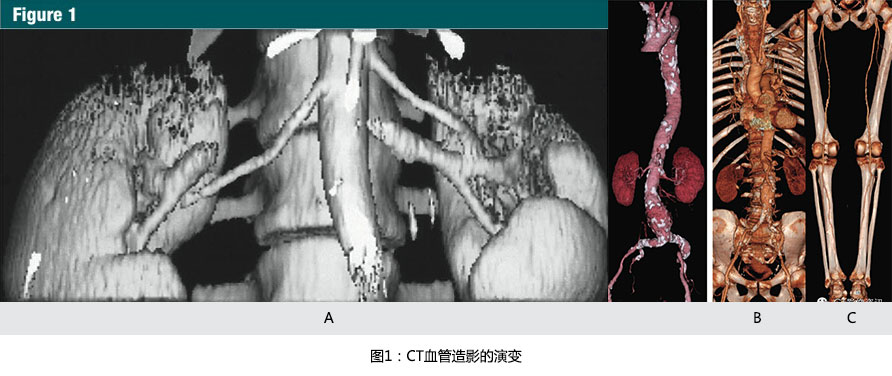

From 1991 to 1998, single-detector row spiral CT technique limitedclinical CT angiography to discrete vascular territories. Prior to the introduction of scan pitch values greater than one, a scan with 3-mm nominalsection thickness provided a maximum of 9 cm table travel in 30 seconds andthus limited initial applications to the extracranial carotid arteries (10),the circle of Willis (11), the renal arteries (12,13)(Fig 1a), and the proximal abdominal aorta(13).

1998年推出的早期多排探測器CT具有4排探測器和0.5s的旋轉(zhuǎn)時(shí)間,對于相同層厚,單位時(shí)間增加了8倍的容積覆蓋范圍(8,23)(圖 1b,1c)。

Early multi-detector row CT scanners introduced in 1998 had four detector rings and were capable of 1/2-second gantry rotations, effectively multiplying volume coverage per unit time 38 at the same section thickness (8,23)(Fig 1b, 1c).

摩爾定律也直接成為CT血管造影(CTA)最終臨床應(yīng)用的推動者:因?yàn)橐粚咏又粚拥腃TA圖像并不有效和直觀,可視化的CT血管造影包括表面遮蓋顯示,最大密度投影,和容積再現(xiàn)(VR)(圖1b,1c)。

Moore's law is also directly responsible for the final enabler of clinicalCT angiography: Because section-by-section inspection of CT angiographic imagesis neither efficient nor intuitive, visualization of CT angiography studies employs shaded surface displays, maximum intensity projections, and volume rendering (Fig 1b, 1c).

(A):1991年12月獲得的腎動脈CT血管造影圖像。9厘米的縱向覆蓋,采用3mm的準(zhǔn)直線束需要30秒螺旋掃描時(shí)間。當(dāng)時(shí),表面遮蓋技術(shù)是唯一的三維顯示手段。最大密度投影和容積再現(xiàn)成像需要在高度專業(yè)的計(jì)算機(jī)系統(tǒng)上進(jìn)行脫機(jī)處理(參考文獻(xiàn)13)

(B):隨著1998年的四排螺旋CT的引進(jìn),使主動脈-髂動脈系統(tǒng)(從胸廓入口開始直到腹股溝)作為一個(gè)整體僅通過一次圖像采集并成像成為了可能。容積再現(xiàn)技術(shù)所展示的CTA圖像,使用4x2.5mm的螺旋掃描模式在28秒內(nèi)掃描完成。圖片充分顯示了主-髂動脈鈣化和腹主動脈瘤(參考文獻(xiàn)8)

(C):2001年使用容積再現(xiàn)技術(shù)展示的CTA圖像,使用16 x1.25毫米螺旋掃描模式,僅用了21秒的時(shí)間,就完成了從顱底至踝的動脈系統(tǒng)掃描,離1991年第一例螺旋CT的CTA成像只隔了10年,但是CT的掃描速度則增加了近25倍。